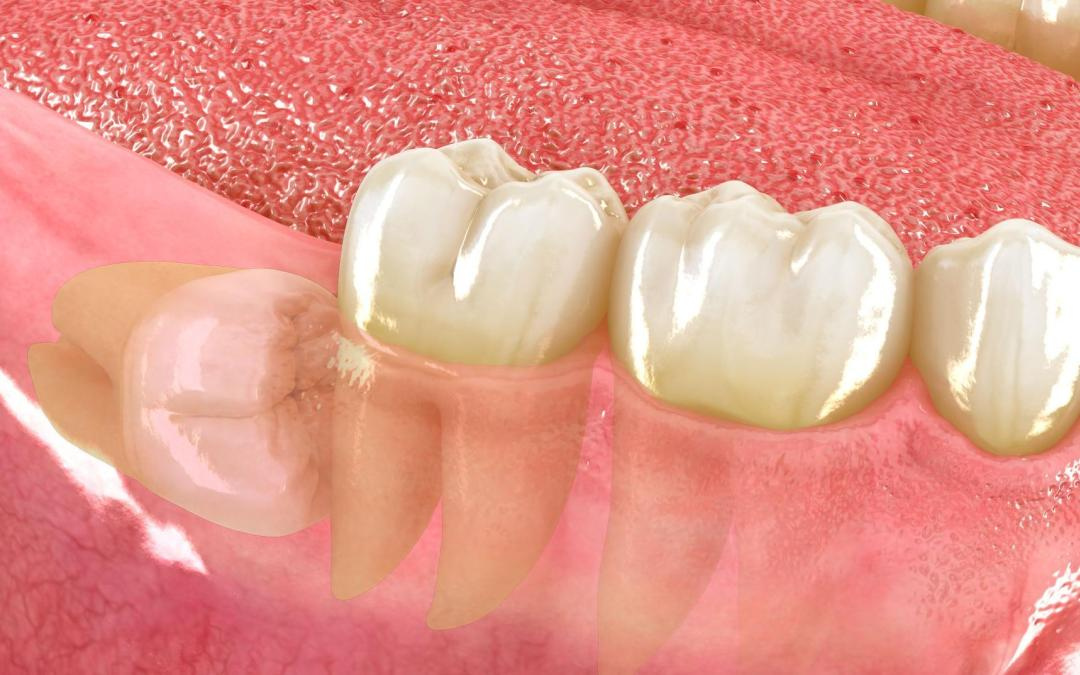

La gingivitis es la inflamación de las encías debido a la acumulación del sarro entre diente y encía provocando la inflamación de las mismas y el sangrado. Si la enfermedad no se resuelve a tiempo y la infección sigue su evolución puede derivar en una periodontitis. En esta fase las encías se retraen y puede dañar el hueso que soporta el diente y favorecer su pérdida.